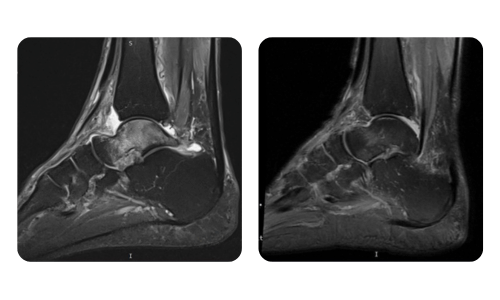

I progressi dei nostri pazienti, misurati prima e dopo la terapia iperbarica, riflettono l'efficacia e l'impatto positivo del trattamento. Scopri i risultati documentati della terapia iperbarica presso la clinica Hyperbarium Oradea, basati su valutazioni cliniche e dati oggettivi che evidenziano miglioramenti significativi in diverse condizioni.